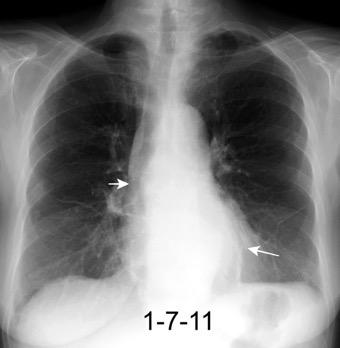

Tromboembolismo pulmonar Diafragma elevado 20%

Atelectasia crónica de LLI en paciente con enfermedad neuromuscular.